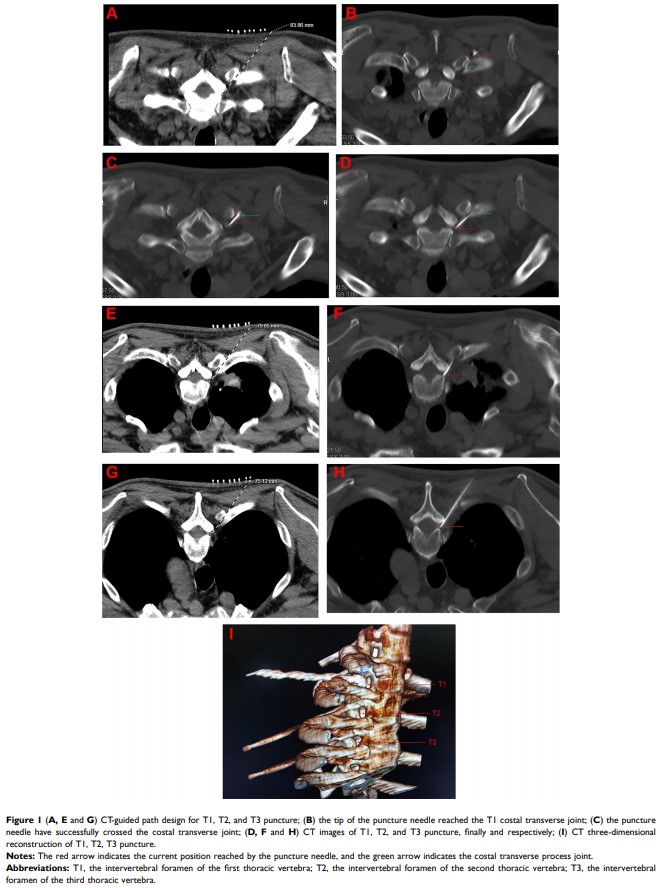

对于接受脉冲射频治疗的 T1-T3 带状疱疹神经痛,肋横突穿刺术的应用及治疗效果